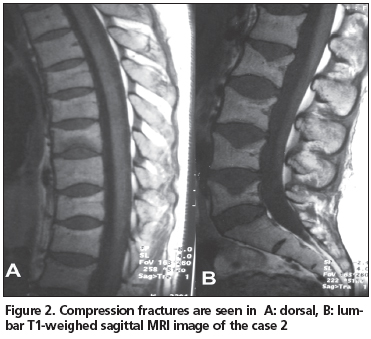

Compressive fractures were detected in nearly all lumbar and thoracic vertebras on magnetic resonance imaging (MRI), requested elsewhere before admission to our clinic; the fractures were most prominent in the lower thoracic and upper lumbar region (Figure 1). Bone mineral density (BMD) examination obtained with dual-energy X-ray absorbtiometry (DXA) (DXA-Lunar) revealed a 34% loss in the lumbar spine and 30% loss in the femoral region with respect to her age group (L2-4 Z-score -3.4, femur neck Z-score -2.4).